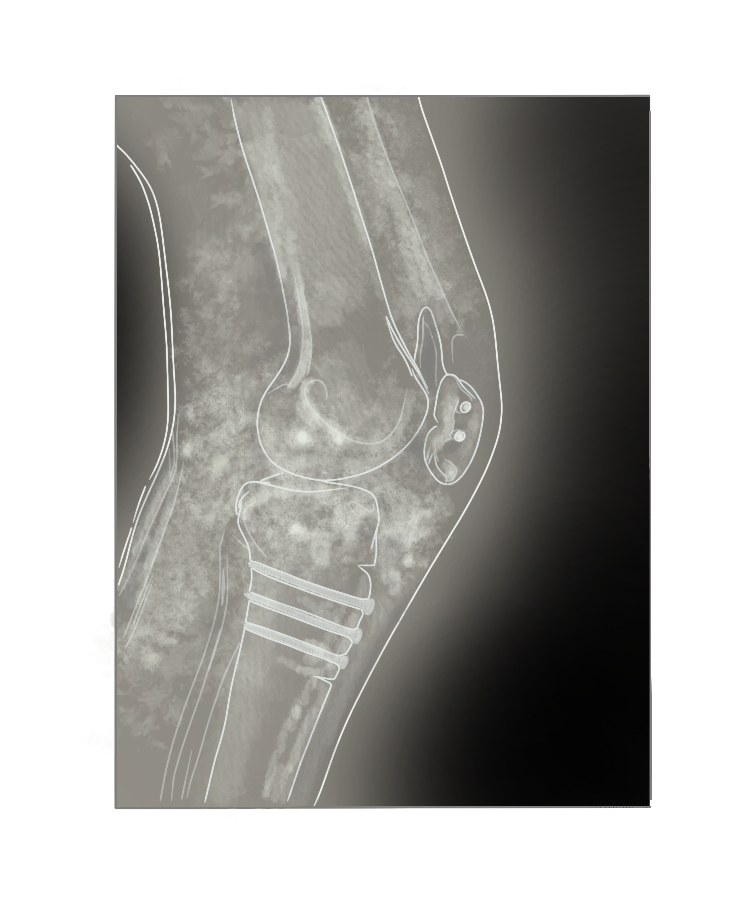

Artrosis severa de rodilla con evidente pérdida del espacio articular

Radiografía con prótesis de rodilla

Si consultas por esta patología, tu médico te preguntará sobre tus actividades diarias, el dolor y la movilidad de tu articulación para determinar conjuntamente la severidad. Luego, se realizarán radiografías de la rodilla para evaluar cuánto ha disminuido el espacio articular, así como una radiografía de las extremidades inferiores (telerradiografía) para objetivar el eje de la extremidad.